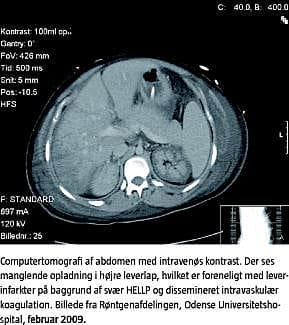

Patienten udviklede fulminant leversvigt med encefalopati og anuri. Der blev opstartet continous renal replacement therapy og plasmaferese. Patientens tilstand bedredes ikke, og hun blev overflyttet til andet tertiært center med henblik på Molecular Adsorbents Recirculating System-behandling . Tilstanden stabiliserede sig på ottendedagen, og den intensive behandling kunne aftrappes. Der var fortsat nyresvigt. Patienten blev i behandlingsforløbet trakeostomeret pga. stort hæmatom i tungebasis, formentligt fra et tungebid under et ubevidnet eklamptisk anfald. Patienten stabiliserede sig og blev udskrevet på 16. dagen fra intensivafdelingen og til hjemmet på 22. dagen.